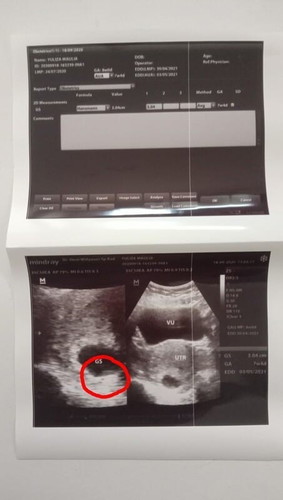

Gini bun, tdi kan saya usg,, Nah kata dokternya rahim saya itu ngadapnya kebelakang, normal sih 70% wanita ngadap ke dpan, dan 30% nya ngadap kebelakang.. Kira" bunda ada yg pernah ngalamin nya ngga? Trus pas ngga d foto bayinya keliatan bun, detak jntungnya juga. Tpi pas d foto bgtu bu 😀 Malah belakangin kya ngga mau d foto bun.. #bantusharing #8weekpregnant